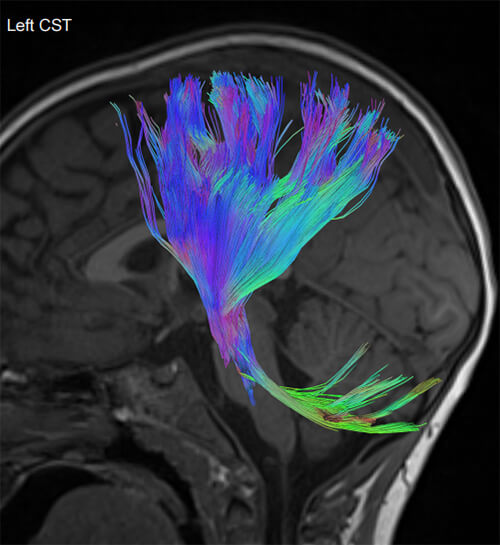

- Ειδικές τεχνικές state-of-the-art (Λειτουργική / Πολυπαραμετρική MRI, Φασματοσκοπία, Δεσμιδογραφία, Δυναμικές Αγγειογραφίες, Νευρογράφημα, Μελέτη Ροής ΕΝΥ)

- Ενσωμάτωση των δεδομένων σε συστήματα νευροπλοήγησης, ώστε ο νευροχειρουργός να αποφεύγει κατά την διάρκεια του χειρουργείου τα λειτουργικά κέντρα του εγκεφάλου (π.χ. κέντρο λόγου και κίνησης) και τη μόνιμη νευρολογική βλάβη

- Δεσμιδογραφία (Τractography)